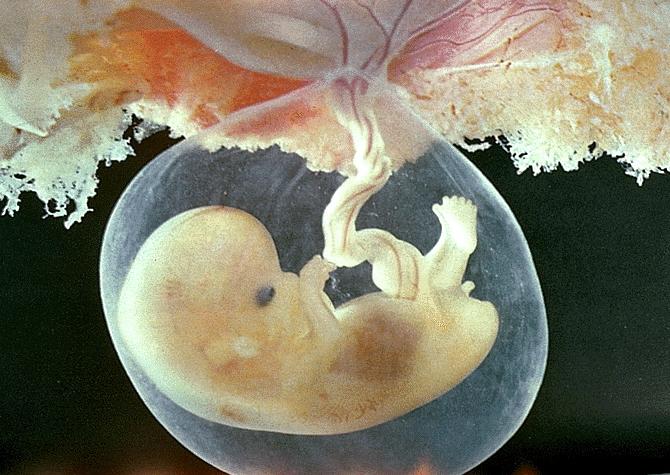

Развитие эмбриона: Что происходит на 3 неделе беременности

Раздел: Фотопанорама